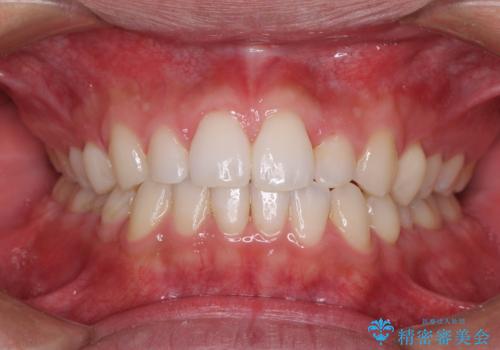

前歯のデコボコとクロスバイト インビザライン矯正治療

- 前歯のデコボコとクロスバイトを治したいとのことで来院された患者様です。

上下顎ともに歯列全体の側方拡大を行い、下顎前歯はIPR(歯と歯の間を削る)によってデコボコとクロスバイトが解消するように設計し、インビザラインにより治療を行うこととしました。

2年弱で終了する予定でしたが、途中来院されなかった時期があり、その後舌側転位している前歯を動かせるところまで動かしたいとのことで4年ほど治療を継続されました。